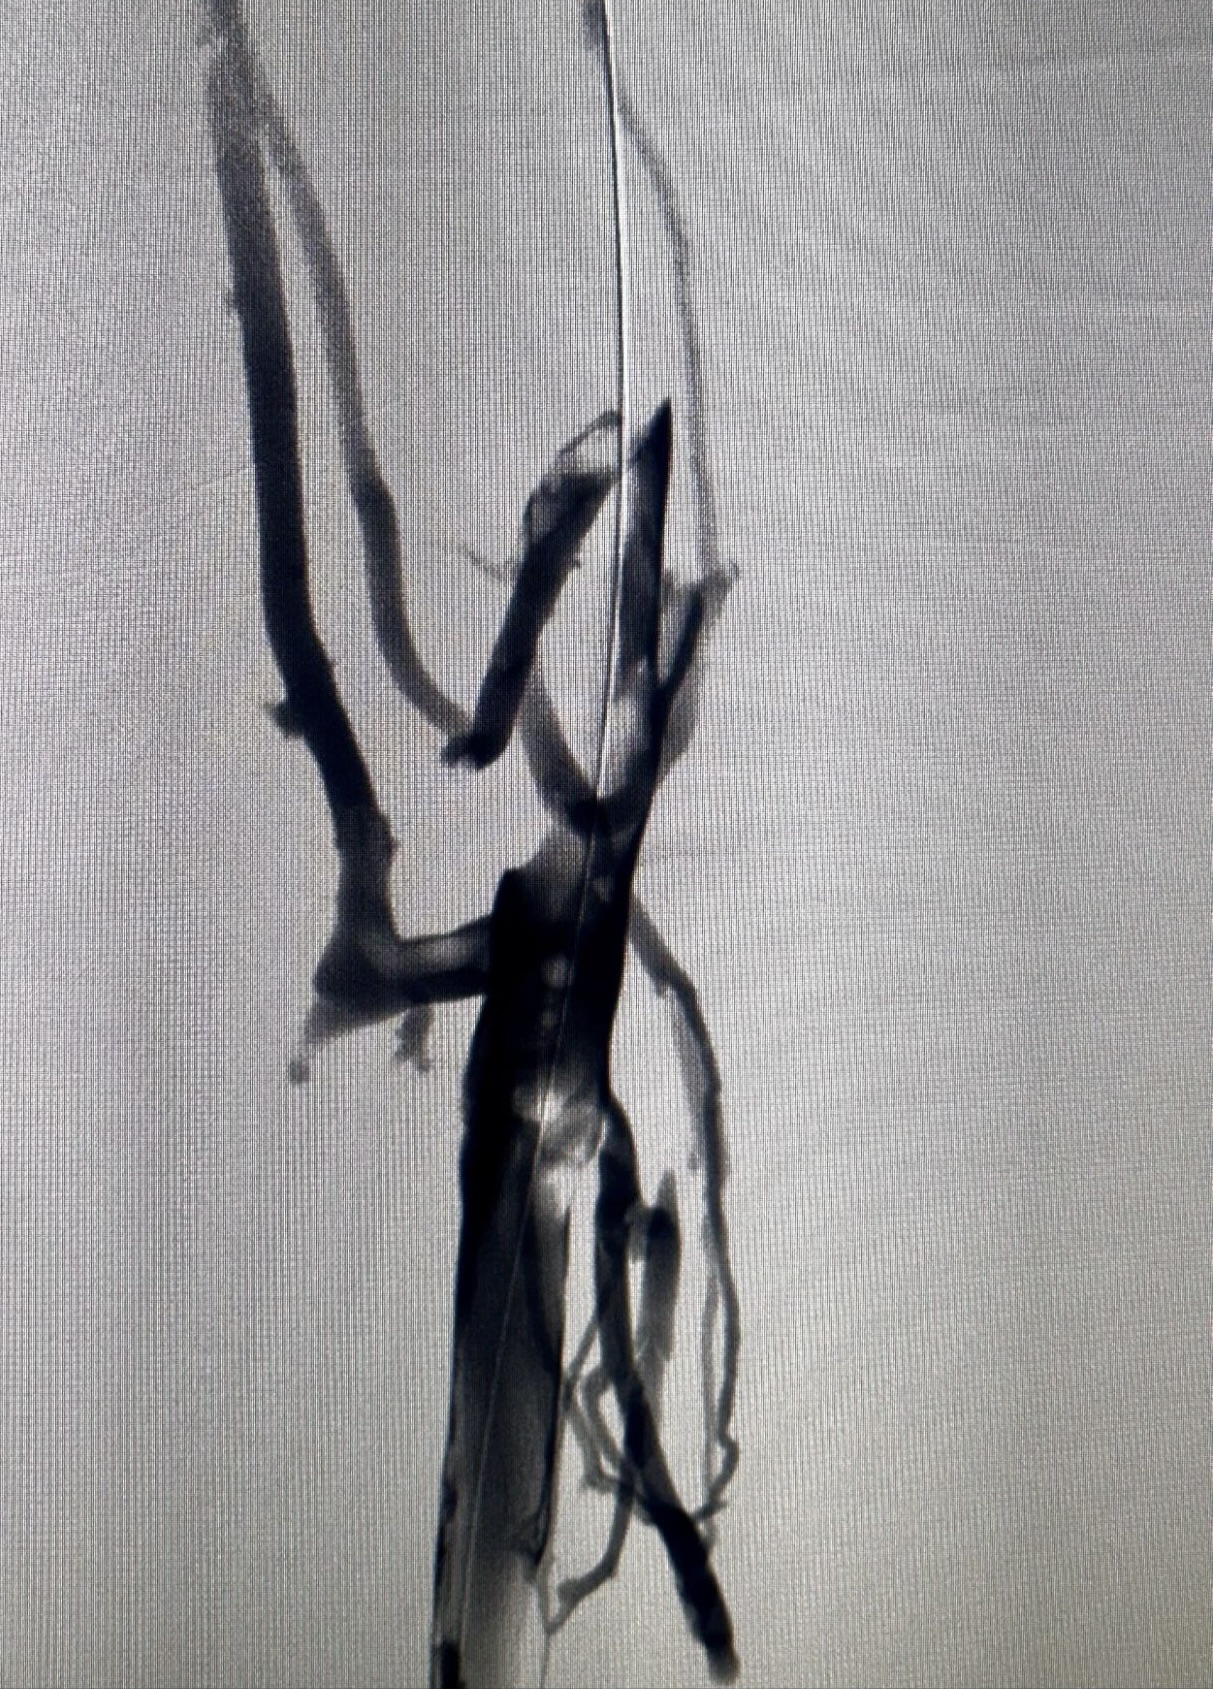

”Rapid Revascularization for Iliofemoral DVT

Acute extensive iliofemoral DVT demands a definitive solution.

The Case: Complete occlusion of the right iliac and femoral veins.

The Procedure:

1. Transpopliteal Access for direct control.

2. Mechanical Thrombectomy using the Penumbra 16 catheter for rapid clot aspiration.

3. Adjunctive Balloon Angioplasty to address underlying venous stenoses and ensure a durable result.

The Outcome: Immediate restoration of flow, resolution of symptoms, and a significant reduction in the risk of Post-Thrombotic Syndrome.

A powerful, minimally invasive approach that changes the patient’s trajectory.”